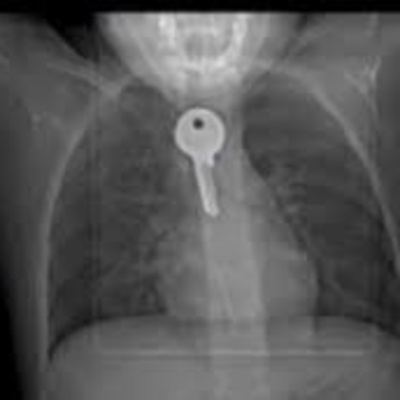

Bắt chước ảo thuật gia nuốt chìa khóa, làm theo hướng dẫn cách tự tử giả bằng dây, nhiều trẻ em đã gặp phải nguy hiểm. Thạc sĩ Trần Thị Thu Hà – quản lý Phòng khám Cây Thông xanh thuộc Trung tâm Nghiên cứu và Đào tạo Phát triển cộng đồng phân tích tâm lý nghịch dại của trẻ em và hướng dẫn bố mẹ cách kiểm soát trẻ. --- Support this podcast: https://anchor.fm/v2eva/support